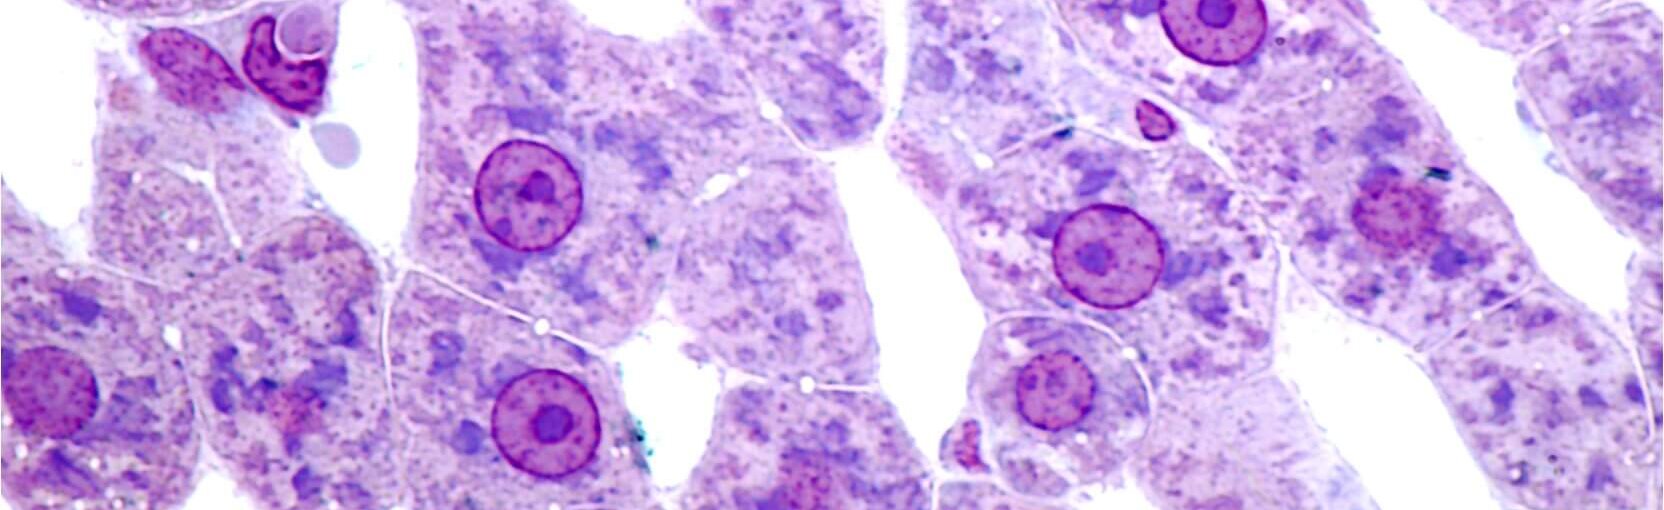

Primary Human Hepatocytes

BeCytes Biotechnologies provides primary human hepatocytes, the gold standard for metabolism, drug-drug interaction, and toxicity studies in in vitro models. These hepatocytes serve as a cornerstone in liver research and drug development, bridging the gap between laboratory studies and the complex functions of the human liver. Various subcategories of these cells cater to specific research needs, enhancing their versatility in scientific applications.